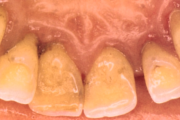

Krooniline parodontiit

Krooniline parodontiit on mikroobide poolt põhjustatud hammaste tugikudede põletik, mille tulemusena tekib progresseeruv alveolaarluu (nähtav röntgenograamil) ja periodontaalligamendi destruktsioon, igemetaskute moodustumine, igeme retsessioon või mõlemad kahjustused kombineeritult. Loe edasi »

Sümptomid:

- igemed veritsevad (19)

- igemed punetavad (21)

- ige on paistes (mädapunn)

- igemed on tursunud/vohavad (17)

- igemed on valulikud (19)

- igemepiir on taandunud (3)

- puudulik suuhügieen (5)

- igemepealne hambakivi (5)

- igemealune hambakivi (4)

- halb hingeõhk / suu haiseb (12)